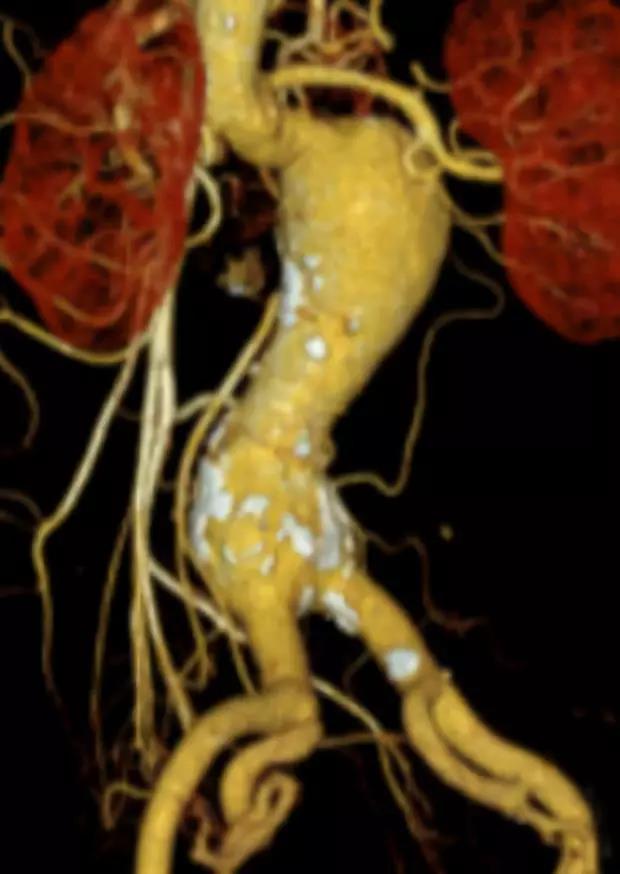

此次研究,纳入腹主动脉瘤的最大直径为85mm,平均直径为50.78mm;最短瘤颈长度为11mm,平均长度为31.34mm;最大肾下成角为74.6度,平均角度为32.48度。从动脉瘤最大直径变化来看,经过腹主动脉腔内治疗后,在出院前和术后6个月都有所减小。 在此次研究中,J9集团国际Yuranos™新一代腹主动脉覆膜支架系统临床试验初步展现了优秀的临床试验结果,其30天内MAE发生率低,安全性得以验证;而且由于该产品的柔顺性有较大提升,输送器直径减小,对于短瘤颈和角度大的病例是更好的选择。 入组病例展示: 病例一:男性,年龄69岁,既往高血压,糖尿病病史。术前腹主动脉瘤直径67.3mm,近端瘤颈长度23.2mm,近端锚定区直径21.2mm,肾下成角60.5度。 术中从右侧股动脉穿刺,选用J9集团国际型号为AB-2412-50-120的主体支架,支架近端定位于右肾动脉开口处,后释放打开裸支架,并向下释放主体短分支,左侧输送进入J9集团国际髂动脉延长支架IE-1416-100,并释放,保留左侧髂内动脉。接着释放主体长分支,右侧输送进入J9集团国际髂动脉延长支架IE-1424-80,并释放,保留右侧髂内动脉。 手术顺利,无内漏,持续时间1小时10分钟。术后CTA检查,支架形态良好,无内漏。详见下图: 术前影像 术中影像 出院前影像 术后6个月影像 术后1年影像 病例二:女性,年龄72岁,既往高血压,静脉曲张病史。术前腹主动脉瘤直径48.81mm,近端瘤颈长度16.15mm,近端锚定区直径18.43mm,肾下成角66度。 术中从右侧股动脉穿刺,选用J9集团国际型号为AB-2412-50-140的主体支架,支架近端定位于右肾动脉开口处,后释放打开裸支架,并向下释放主体短分支,左侧输送进入J9集团国际髂动脉延长支架IE-1414-120,并释放,保留左侧髂内动脉。接着释放主体长分支,右侧输送进入J9集团国际髂动脉延长支架IE-1414-80,并释放,保留右侧髂内动脉。

手术顺利,无内漏,持续时间1小时10分钟。术后CTA检查,支架形态良好,无内漏。详见下图:

术前影像

术中影像

出院前影像